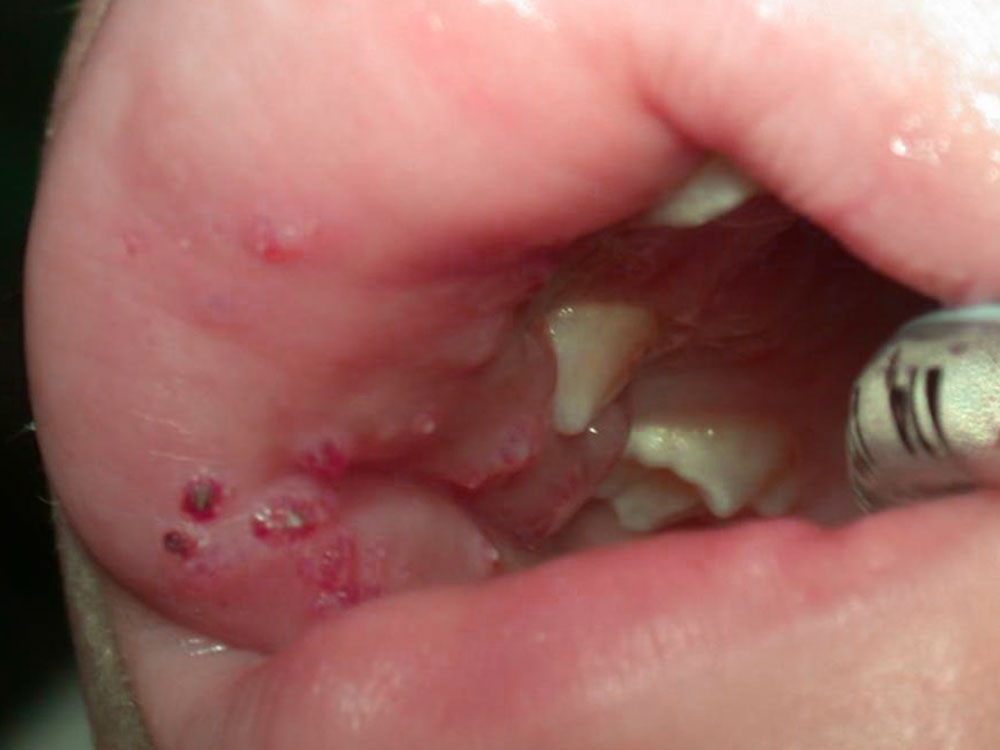

Initially they are filled with clear lymph and, as they progress, they are increasingly intermingled with blood and then become shimmering red.

Similarly, vesicles filled with clear or bloody lymph may appear on the body of the tongue and sublingually in the mucosa, sometimes combined with further vesicular rashes on the mucosa of the cheek pouches.